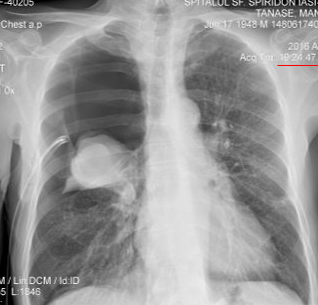

Rx toracică, incidență P-A

DESCRIERE: DAS + stază

indice cardiotoracic ↑

semne de dilatare a AS:

dublu contur inferior drept (contur dublu “festonat“)

deschiderea unghiului de bifurcație a traheei >120 grade

bombarea arcului mijl stg (golful pulm) → HTP

semne de stază pulm: dilatarea hilurilor + apicalizarea circulației + linii Kerley B

DX: stenoză mitrală

DD: insuf mitrală, boală mitrală, stenoză Ao